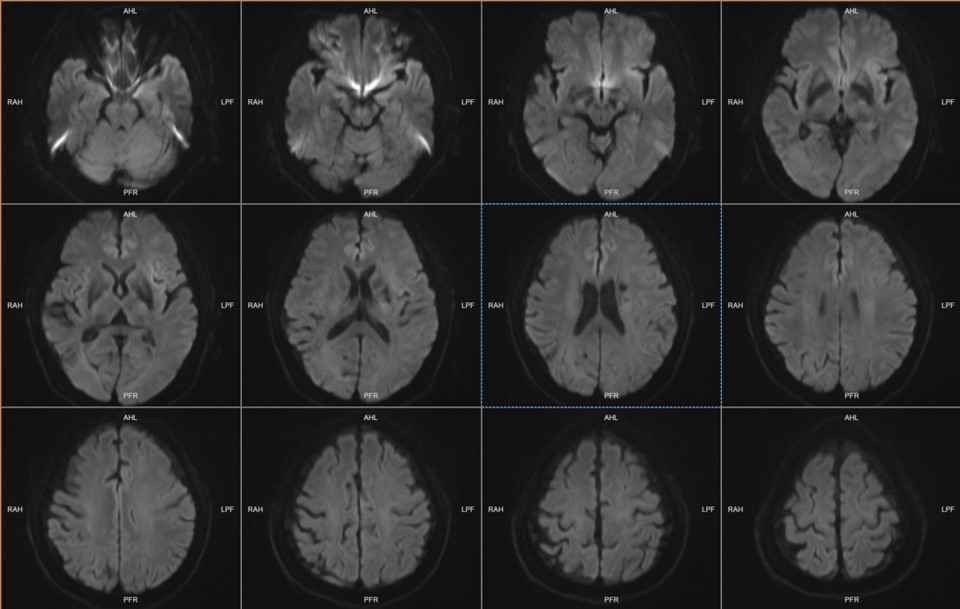

FLAIR显示左侧脑室旁陈旧性梗死灶;右侧脑室后角顶下小叶梗死灶。

DWI显示无急性梗死灶